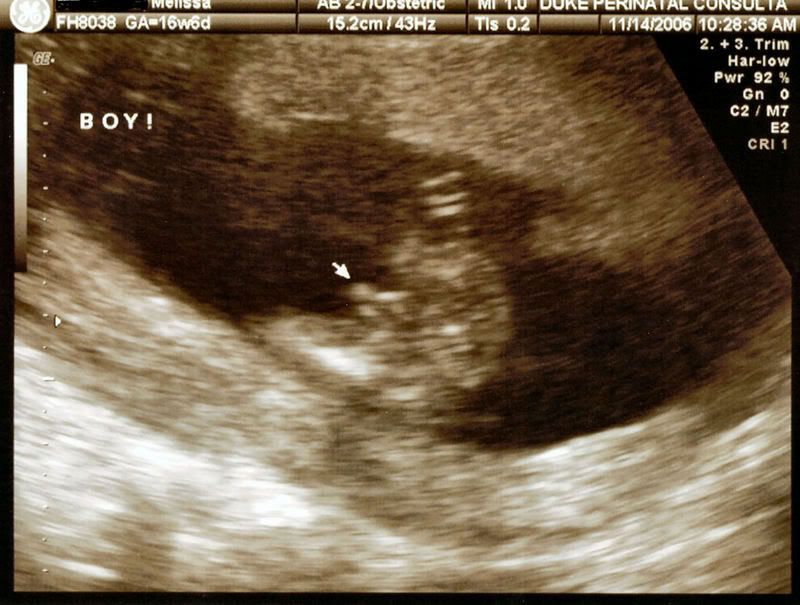

My daughter had her 18 week ultrasound today and we have a little boy. He was quite proud to display his little tallywhacker at the appropriate moment. We are so thrilled and tickled that he seems very happy and healthy. As soon as I get the pictures loaded onto photo bucket I will post the handsome little devils pictures. |

here he is asleep http://i11.photobucket.com/albums/a190/the...b4fan/Sleep.jpg from the side with his little hand open http://i11.photobucket.com/albums/a190/the...an/openhand.jpg Here is his little face http://i11.photobucket.com/albums/a190/the...4fan/Face-1.jpg He had ginormous feet http://i11.photobucket.com/albums/a190/the...ab4fan/Foot.jpg His defining moment http://i11.photobucket.com/albums/a190/the...fab4fan/Boy.jpg |